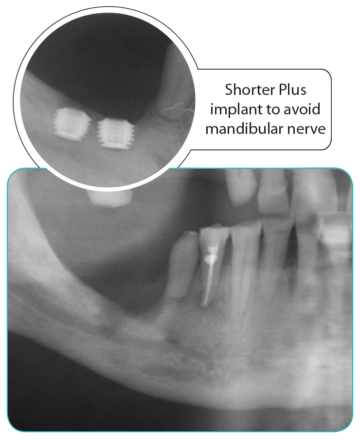

I nuovi impianti Shorter e Shorter Plus sono una evoluzione degli impianti a PLATEAU con fissaggio Press-fit e sono stati studiati e perfezionati da un team di ingegneri svizzeri allo scopo di migliorarne forma e superficie perchè il design di un impianto ne determina le capacità cliniche